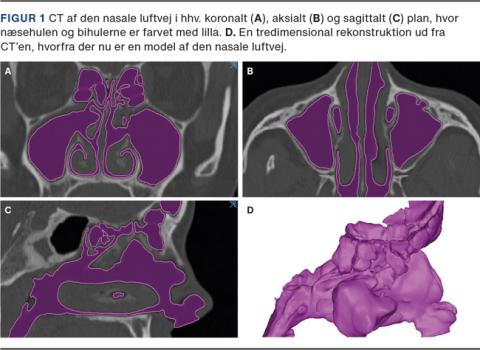

Nasal-CFD baseres hyppigst på en CT af næse- og bihulesystemet (Figur 1), men kan også udføres ud fra en MR-skanning. Denne bearbejdes og segmenteres med software, der danner en virtuel tredimensional (3D)- rekonstruktion, som er opbygget af flere hundredetusinde til millioner af de celler [7] (Figur 2), der danner slimhindeoverfladernes afgrænsning for den komplekse anatomi i næsen. Der kan nu udføres forskellige computersimuleringer på 3D-modellen, hvor man forud for dette har sat randbetingelser for bl.a. temperaturer, trykforhold samt type og hastighed af luftstrøm igennem næsen for at simulere nasal vejrtrækning. Disse computersimuleringer kaldes CFD, der giver mulighed for at undersøge, hvordan luftstrømmen meget præcist fordeler sig i næse-bihule-systemet hos den specifikke patient, og hvilke afledte effekter det giver. CFD udmærker sig ved, at man får en nøjagtig grafisk fremstilling af dette, og hvilke steder i næsen der har størst indvirkning på dette. Således giver CFD et langt mere detaljeret og nuanceret billede af fysiologien i næsen, end det tidligere muligt at få. Software kan nu ændre i 3D-modellen, så man kan simulere kirurgi i næsen og herefter afprøve effekten med CFD, hvilket muliggør virtuel kirurgi.